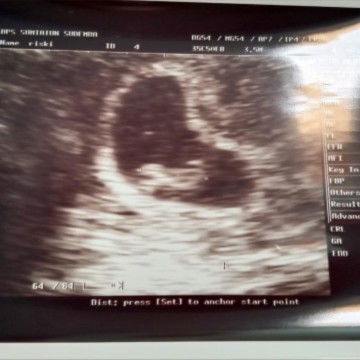

alhamdulilah usia 8w janin udh mulai kelihatan

Alhamdulillah π€